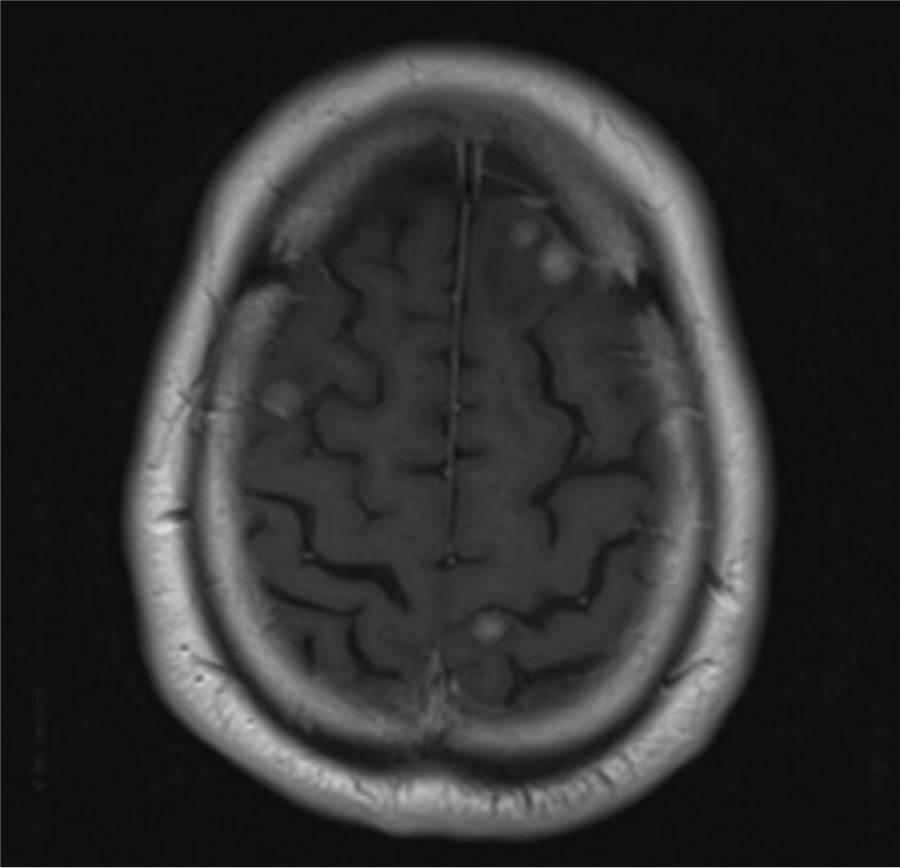

En la analítica destacaron valores elevados de PSA (6,33 ng/ml) y fibrinógeno (647,95 mg/dl), sin otras alteraciones relevantes. Posteriormente se realizaron una resonancia magnética cerebral y una tomografía computarizada cervical, torácica, abdominal y pélvica. Ambas pruebas revelaron múltiples metástasis localizadas en cerebro, pulmón, hueso, partes blandas, suprarrenales, hígado y vesícula.

RM cerebral que muestra múltiples metástasis nodulares con edema perilesional.